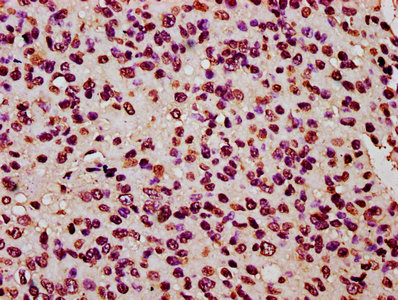

• IHC image of CSB-PA010403OA120nhibHU diluted at 1:20 and staining in paraffin-embedded human glioma performed on a Leica BondTM system. After dewaxing and hydration, antigen retrieval was mediated by high pressure in a citrate buffer (pH 6.0). Section was blocked with 10% normal goat serum 30min at RT. Then primary antibody (1% BSA) was incubated at 4°C overnight. The primary is detected by a biotinylated secondary antibody and visualized using an HRP conjugated SP system.